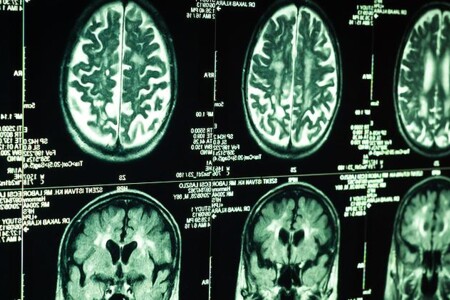

Bolest je nepříjemný pocit, zkušenost sestávající z odpovědi na škodlivý podnět. Je to obranný mechanismus organismu před poškozením či zraněním. Bolest vzniká drážděním nervových zakončení v kůži a v orgánech, které pomocí nervových vláken vysílají vzruch do míchy a vyšších struktur v mozku.